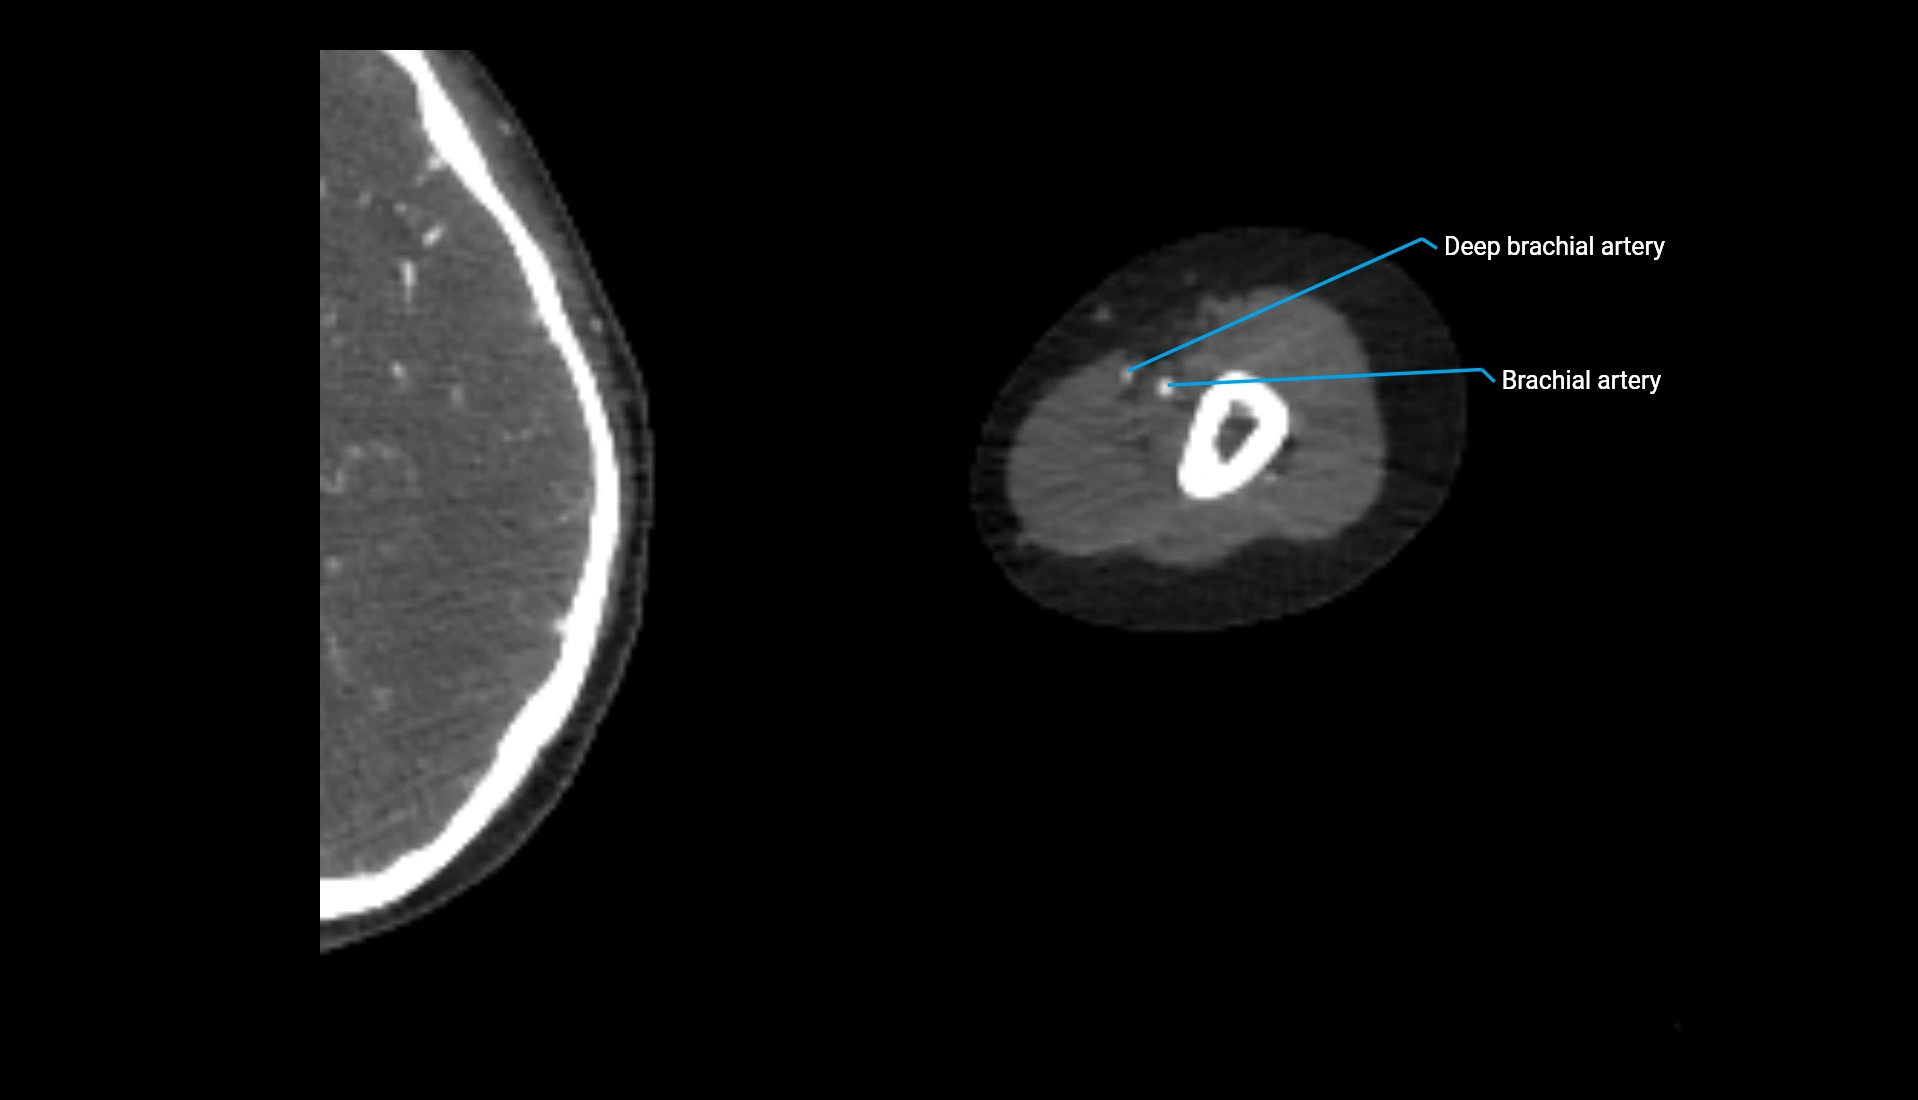

CT Appearance

Non-Contrast CT:

• Cortex: High-density, sharply defined

• Subchondral bone: Dense cancellous matrix

• Articular surface: Smooth concave contour articulating with the capitellum

• Excellent for evaluating bone integrity, alignment, and subtle fractures